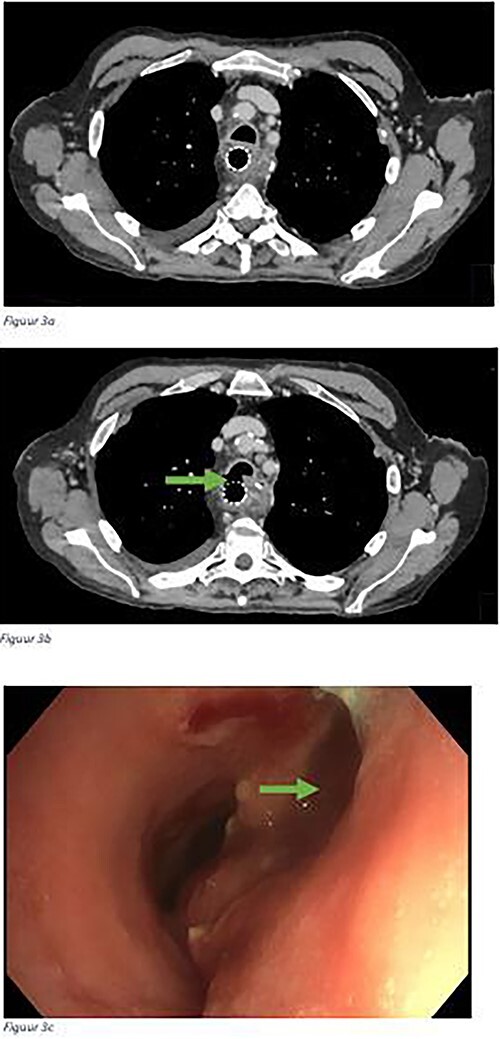

The aim of this study was to evaluate the surgical treatment of esophago-tracheobronchial fistulas (ETBFs) that occurred after esophagectomy with gastric conduit reconstruction in a tertiary referral center for esophageal surgery. All patients who underwent surgical repair for an ETBF after esophagectomy with gastric conduit reconstruction were included in a tertiary referral center. The primary outcome was successful recovery after surgical treatment for ETBF, defined as a patent airway at 90 days after the surgical fistula repair. Secondary outcomes were details on the clinical presentation, diagnostics, and postoperative course after fistula repair. Between 2007 and 2022, 14 patients who underwent surgical repair for an ETBF were included. Out of 14 patients, 9 had undergone esophagectomy with cervical anastomosis and 5 esophagectomy with intrathoracic anastomosis after which 13 patients had developed anastomotic leakage. Surgical treatment consisted of thoracotomy to cover the defect with a pericardial patch and intercostal flap in 11 patients, a patch without interposition of healthy tissue in 1 patient, and fistula repair via cervical incision with only a pectoral muscle flap in 2 patients. After surgical treatment, 12 patients recovered (86%). Mortality occurred in two patients (14%) due to multiple organ failure. This study evaluated the techniques and outcomes of surgical repair of ETBFs following esophagectomy with gastric conduit reconstruction in 14 patients. Treatment was successful in 12 patients (86%) and generally consisted of thoracotomy and coverage of the defect with a bovine pericardial patch followed by interposition with an intercostal muscle.

本研究的目的是评估一家三级食管外科转诊中心对食管胃导管重建术后食管气管支气管瘘(ETBF)的手术治疗。该三级转诊中心纳入了所有在食管切除术和胃导管重建术后因 ETBF 而接受手术修复的患者。主要结果是 ETBF 手术治疗后的成功康复,即手术修复瘘管后 90 天气道通畅。次要结果是瘘管修补术后的临床表现、诊断和术后疗程的详细情况。2007 年至 2022 年间,共有 14 名患者接受了 ETBF 手术修复。14 名患者中,9 人接受了食管切除术并进行了颈部吻合术,5 人接受了食管切除术并进行了胸内吻合术,术后 13 人出现了吻合口漏。手术治疗包括:11 名患者采用开胸手术,用心包补片和肋间肌瓣覆盖缺损处;1 名患者采用补片,但未插入健康组织;2 名患者通过颈部切口仅用胸肌瓣修复瘘管。手术治疗后,12 名患者痊愈(86%)。两名患者(14%)因多器官功能衰竭而死亡。这项研究评估了 14 名患者在食管切除术后进行胃导管重建手术修复 ETBF 的技术和效果。12 名患者(86%)的治疗取得了成功,一般包括开胸手术和用牛心包补片覆盖缺损,然后用肋间肌进行插补。